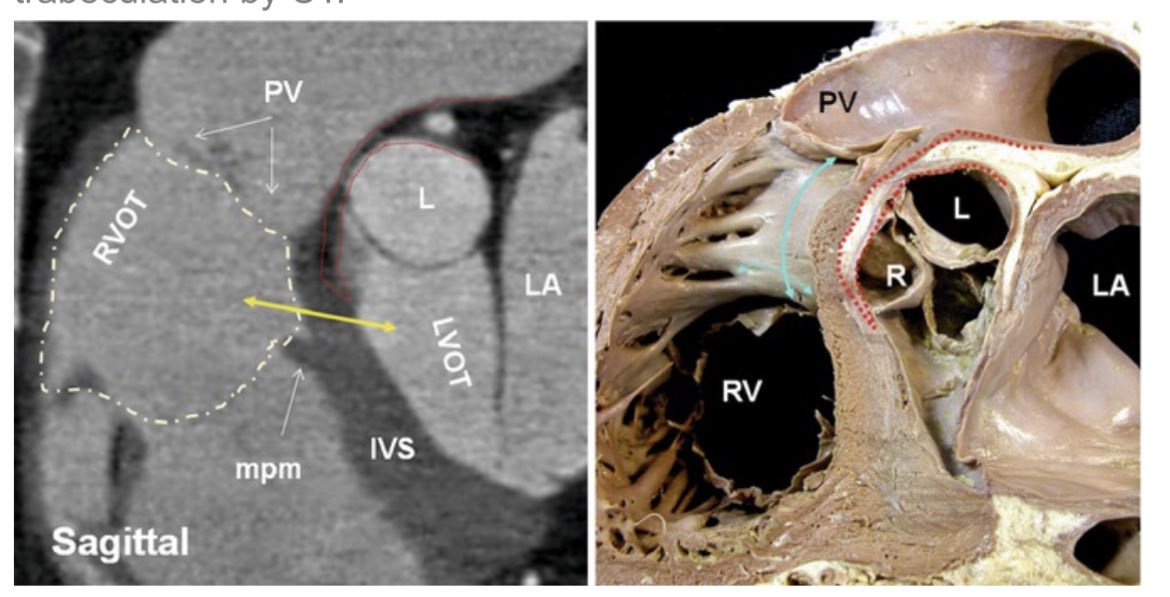

PVC with abrupt V3 transition suggested L-R interleaflet triangle exit. Broad left sided early activation and poor pace mapping. Got it from below pulmonic valve w/ 98% match. Anatomy relationship always an a-ha moment. Excellent mapping Brock Gambill George Crowell #EPeeps

Abrupt V3 transition with V2 pattern break, and this time got it from R-L interleaflet triangle (ILT) within seconds. 27 ms pre-QRS. V2 pattern break so likely too close to pLAD from GCV/AIV, so didn’t waste time there. Great mapping George Crowell #EPeeps